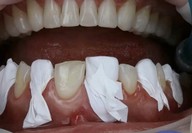

► Tecniche di isolamento dentale

► Procedura clinica per trattamenti full-mouth

Galleria fotografica